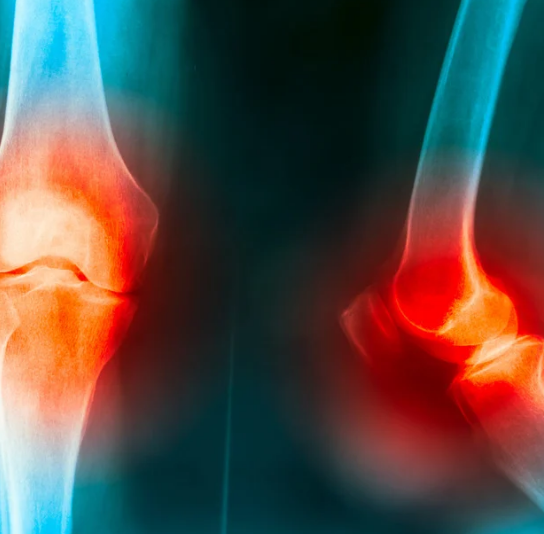

특히 관절 통증, 무릎 뻣뻣함, 관절 운동 제한 등으로 불편을 겪는 중장년층 사이에서 높은 인지도를 보이고 있는데, 정작 어떤 성분이 들어 있는지, 실제 어떤 효과가 있는지 정확히 알고 먹는 사람은 많지 않습니다.

1) 관절통 완화 및 운동 범위 개선

MSM(식이유황)은 연골 내 염증 매개체 생성을 억제하고, 통증 완화 및 관절 유연성 개선에 도움을 줄 수 있습니다. *Journal of International Society of Sports Nutrition (2004)*에서는 MSM 섭취군에서 관절통 및 경직감이 유의하게 감소한 결과가 발표된 바 있습니다.